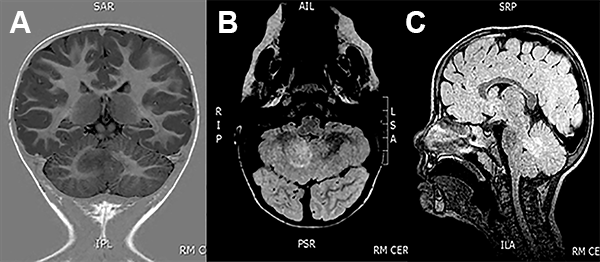

EEG de scalp normal. La RMN de encéfalo mostró una lesión expansiva en la profundidad del hemisferio cerebeloso derecho, en contacto con el pedúnculo cerebeloso superior, con mínimo efecto de masa y sin realce con el contraste (fig. 3).

Figura 3: Caso 2. Imágenes preoperatorias.

A los 29 meses de edad se realizó una exéresis subtotal de la lesión a través de un abordaje suboccipital telovelar (fig. 4). Durante el procedimiento se realizó elecrocorticografía (ECoG), con un electrodo profundo colocado bajo guía ecográfica intraoperatoria que no mostró patrones patológicos. La experiencia en ECoG cerebelosa es escala o nula, por lo tanto se hace muy difícil su interpretación(fig. 5).

Figura 4: Caso 2. Ecografia intraoperatoria.

Figura 5: Caso 2. Imágenes postoperatorias.